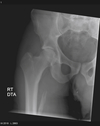

12

Describe this fracture?

A

DASHBOARD

- Fracture of the posterior rim of the acetabulum

- a seated passenger striking the knee on a dashboard, driving the head of the femur into the acetabulum

How well did you know this?